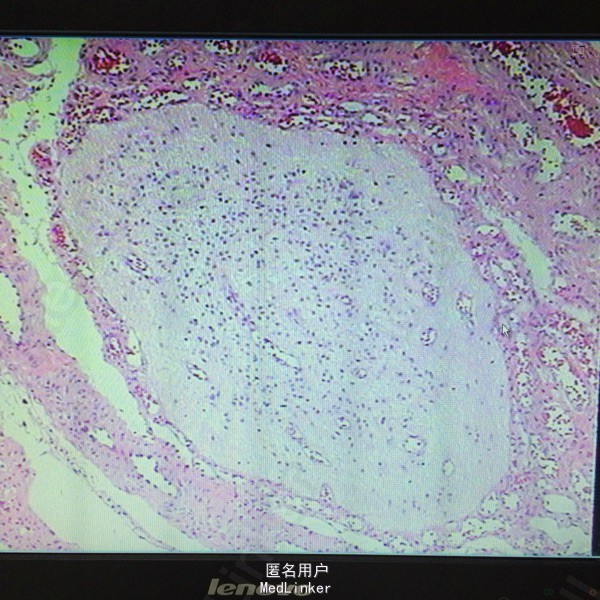

诊断:后枕部脑脊膜膨出 处理:行脑脊膜膨出修补术,病理提示符合脑脊膜膨出